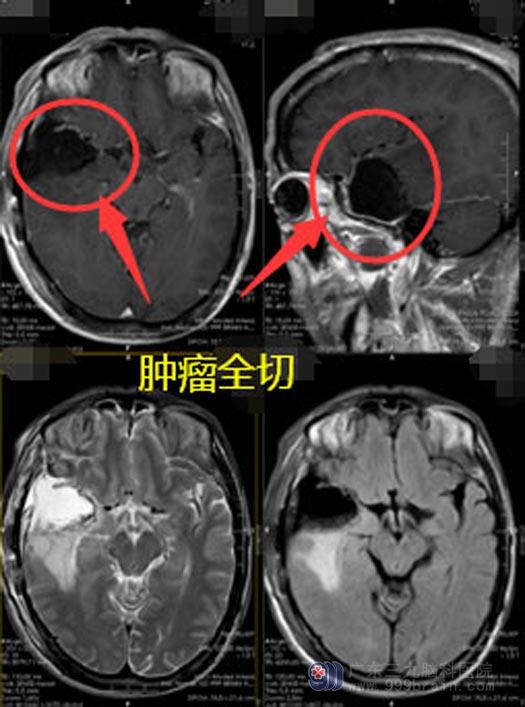

由于当地医院的医疗条件有限,谢先生和家人一起来到了广东三九脑科医院。入住神经外五科后,进一步头颅MR检查提示:右侧颞叶占位性病变,考虑高级别胶质瘤可能性大,完善DWT+ASL+MRS检查后,考虑为右侧颞叶胶质母细胞瘤。

由医院副院长、神经外五科主任鲁明主刀为谢先生实施了“右侧颞叶占位切除术+硬脑膜修补”;术中导航定位,打开皮层可见胶冻状肿瘤,在显微镜下将瘤体分块全切除。经过12个小时的奋战,谢先生安全返回病房。麻醉清醒后,谢先生可以自动睁眼、对答准确、遵嘱活动、四肢肌力肌张力正常,术前担心的并发症均未发生。